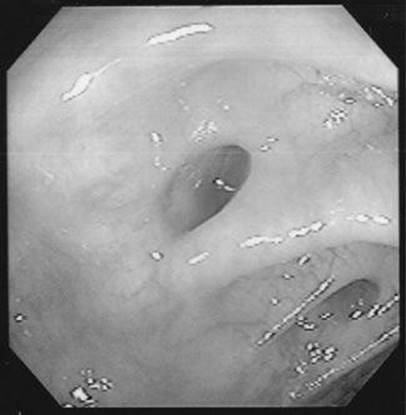

In a patient with melena but a normal hematocrit, the lesion below was found on upper endoscopy. Based on its appearance, what is the approximate risk of rebleeding from this lesion?

Figure 1-3 See also color plate.

The risk of rebleeding in an ulcer with a flat pigmented spot is about 10%.